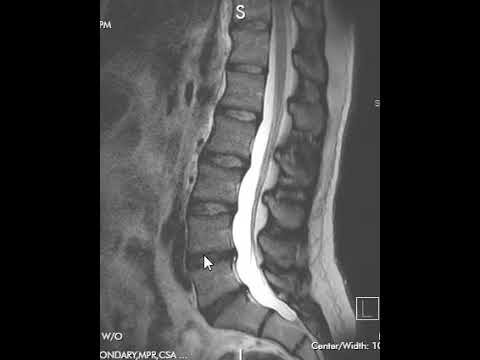

Как читать МРТ поясничного отдела позвоночника | Первый взгляд на МРТ